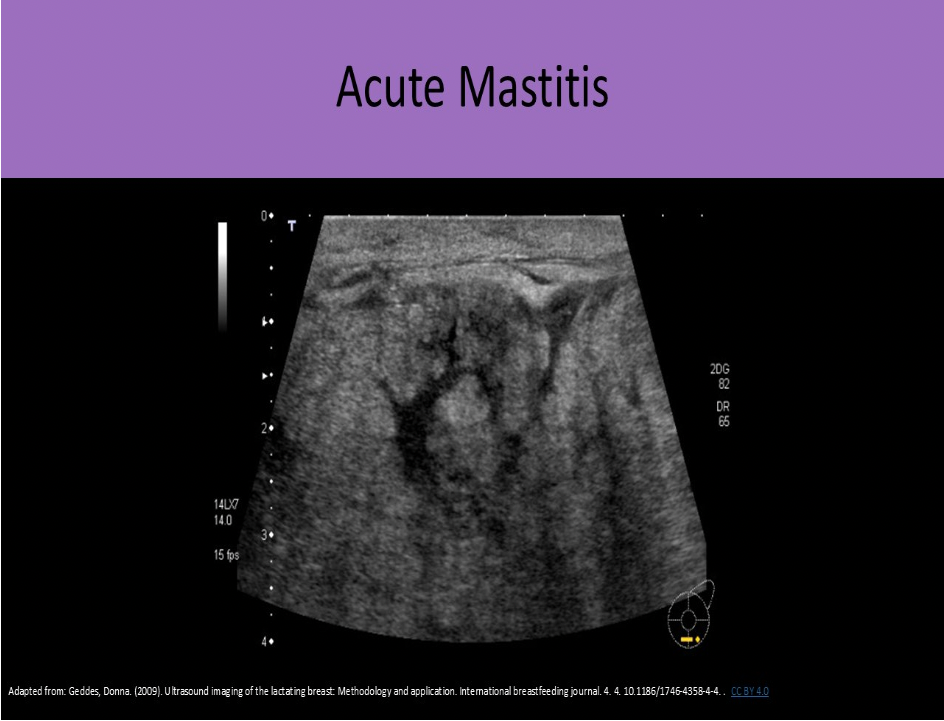

What changes occur on the US image when scanning breast tissue affected by acute mastitis?

C. decreased penetration due to tissue edema

Fluid in the breast tissues will cause an increase in the sound attenuation. This attenuation will reduce penetration and resolution.